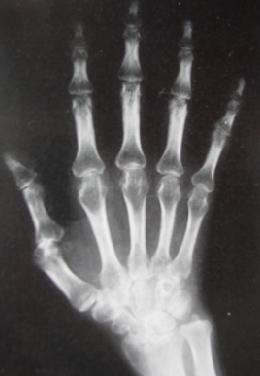

4年前,袁女士感到膝盖疼痛,袁女士以为是自己年龄大了,腿不好使了,只是涂了点药膏。两个月后,膝盖突然剧痛,半个多小时都站不起来,经过X线检查,发现袁女士的膝盖,手指关节骨间隙出现了问题,在经过类风湿因子和血沉的进一步检查,最后确诊是类风湿性关节炎。在往后的治疗中,袁女士也是靠药物来止痛,可是疼痛并没有因此而消失,反而一次比一次厉害,最后来到我院风湿专病科室接受治疗。

(图:袁女士到院时X光显示风湿症状严重)